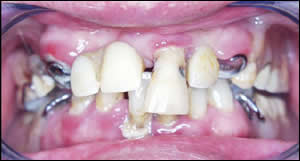

Fig 1: A 54 year old male presented with extensive tooth decay, periodontal disease and partial dentures.

Fig 2: Upper partial denture removed.